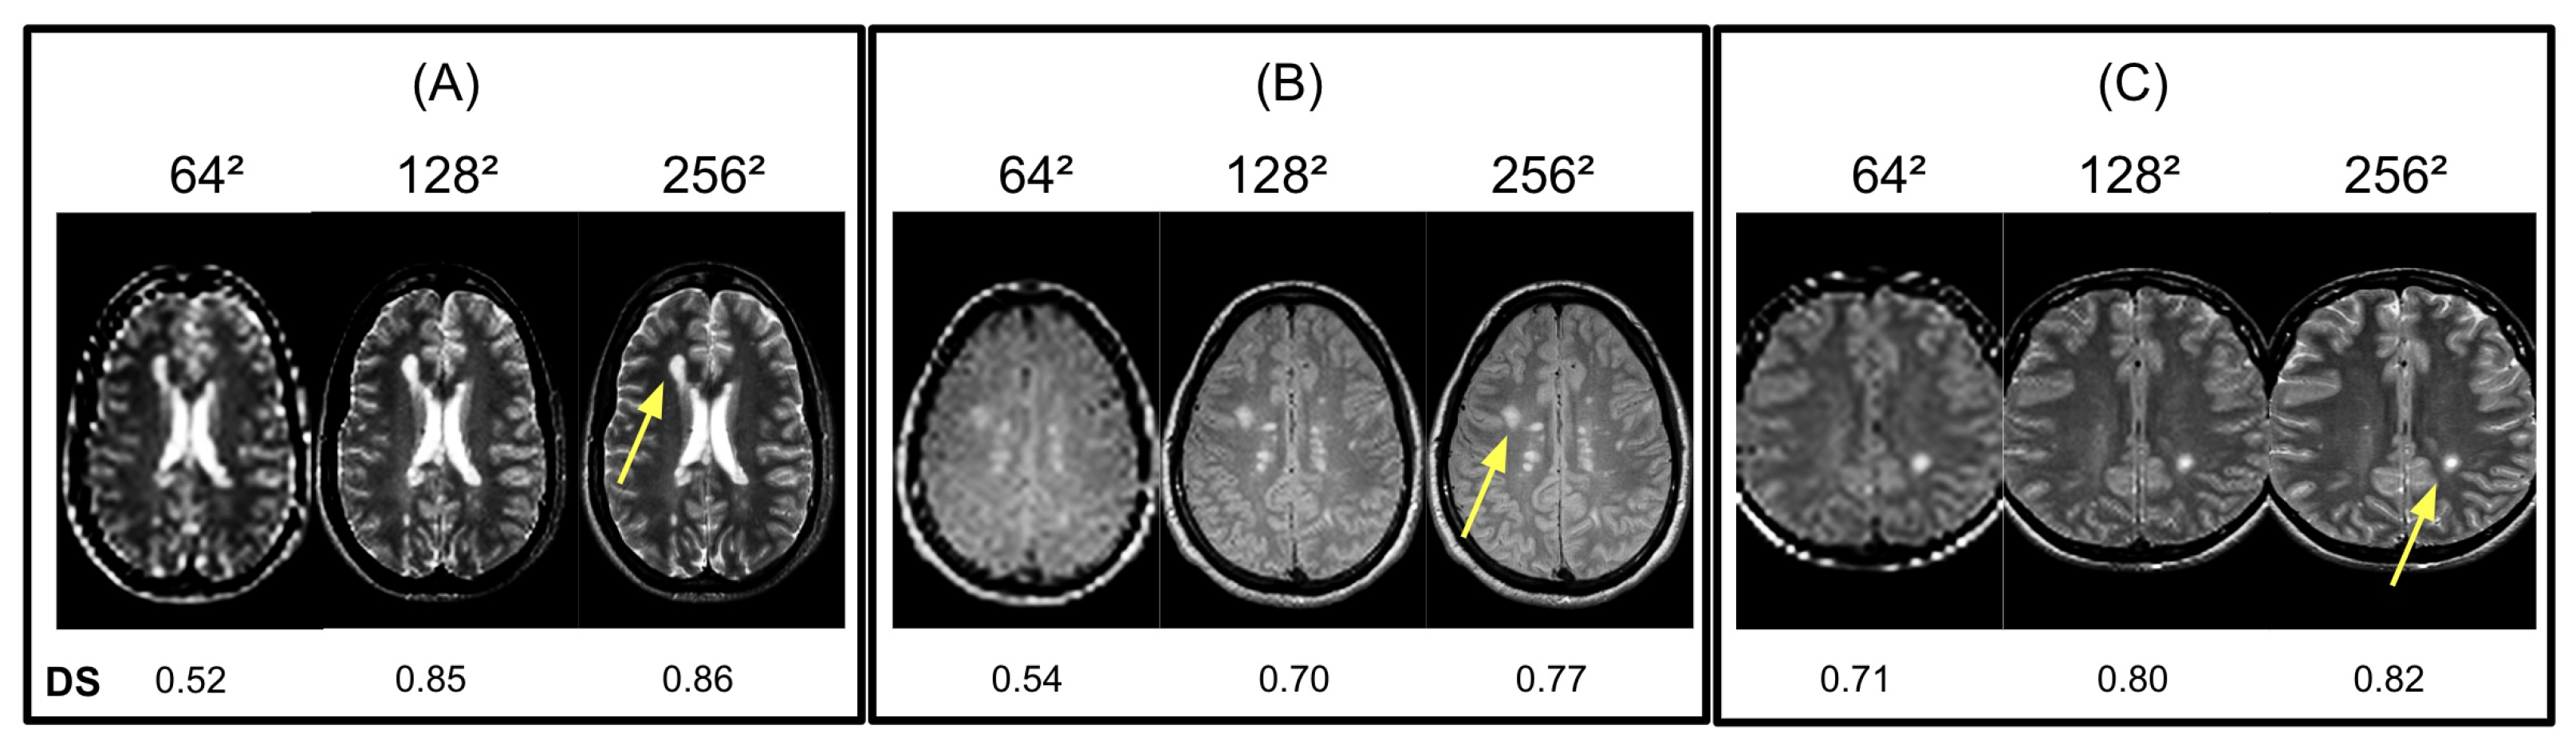

Due to high computational times in testing Isomap and LLE on original brain MR images, we initially reduced the input resolutions. However, Figure 5 shows that reducing the input resolution of LLE and Isomap degrades both methods’ ability to provide accurate DS scores due to the blurring of active lesion boundaries. Our results suggest that Isomap and LLE are able to segment active lesions given 1282 input images but achieve optimal performance on the original 2562 input resolution. As a result, we chose 2562 as the input resolution for LLE and Isomap to obtain accurate DS measurements.

Figure 5. Examples of LLE algorithm sensitivity to different image matrix sizes and resolutions. We compared the active lesion (yellow arrow) in the embedded image to ground truth lesions using DS scores. (AC) As shown in 642 images, (bottom row) DS was significantly lower. However, no significant differences were observed between 2562 and 1282.